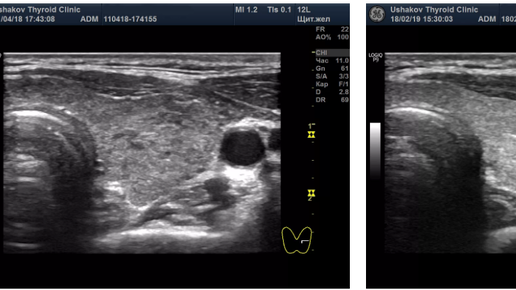

Врачи назначают при гипертиреозе тиреостатические средства, называя это лечением. Но даже руководства и протоколы по эндокринологии чётко сообщают о том, что тиреостатические препараты не оказывают лечения. Какова же роль тиреостатиков и как излечиться при этом заболевании? Американские врачи постарались запутать своих коллег и пациентов смешав два понятия - гипертиреоз и тиреотоксикоз. Расставим точки. Гипертиреоз - это избыток щитовидных гормонов, а тиреотоксикоз - это вредное влияние избытка гормонов...